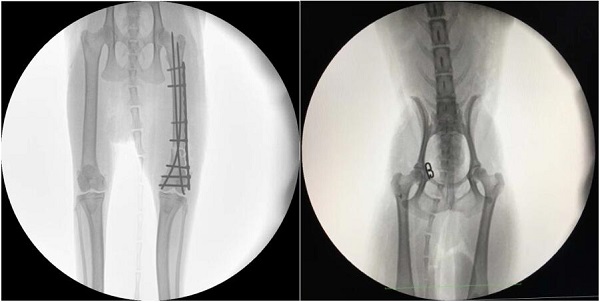

【寵物c臂機臨床圖像】